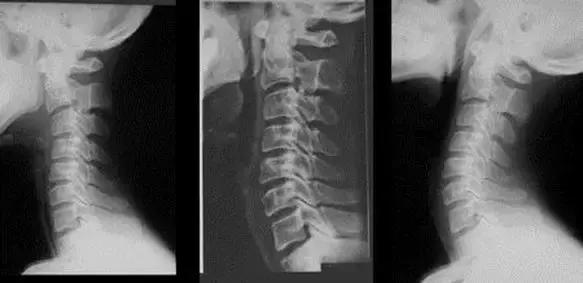

邻居李大爷去串门时看到王阿姨这种状态,推荐她去骨科医院就诊。因为一年前李大爷也有类似症状,手术治疗后症状消失。王阿姨半信半疑来到北京德尔康尼骨科医院,经检查考虑交感型颈椎病,建议颈椎硬膜外药物治疗。王阿姨网上查询发现自己的症状和交感型颈椎病确实相似,于是住院进行了治疗。

其中交感型颈椎病由于椎间盘退变和节段性不稳定等因素,从而对颈椎周围的交感神经末梢造成刺激,产生交感神经功能紊乱。由于椎动脉表面富含交感神经纤维,当交感神经功能紊乱时常常累及椎动脉,导致椎动脉的舒缩功能异常。因此交感型颈椎病在出现全身多个系统症状的同时,还常常伴有椎-基底动脉系统供血不足的表现。

诊 断

诊断较难,目前尚缺乏客观的诊断指标。

出现交感神经功能紊乱的临床表现、影像学显示颈椎节段性不稳定。对部分症状不典型的患者,如果行颈椎高位硬膜外封闭后,症状有所减轻,则有助于诊断。